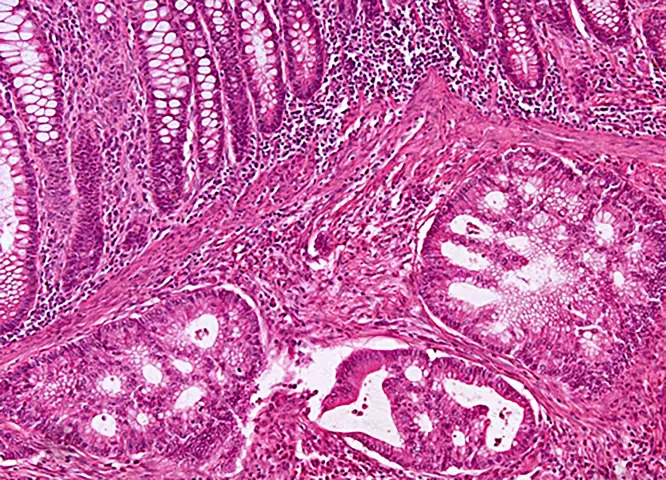

Die feingewebliche Untersuchung (Histologie) ist eine ergänzende Maßnahme bei vielen unserer endoskopischen Untersuchungen oder Punktionen. Durch sie lässt sich zuverlässig eine Krankheit nachweisen oder ein Verdacht ausräumen. Desweiteren kann in Zusammenschau mit anderen klinischen Daten der Schweregrad einer Erkrankung festgelegt werden, was für weitere Therapiekonzepte von großer Bedeutung ist. Wir arbeiten auf diesem Feld seit Jahren mit der Gemeinschaftspraxis für Pathologie Dr. med. Hölzl und Dr. med. Eisenlohr und Dr. med. Assmann zusammen.